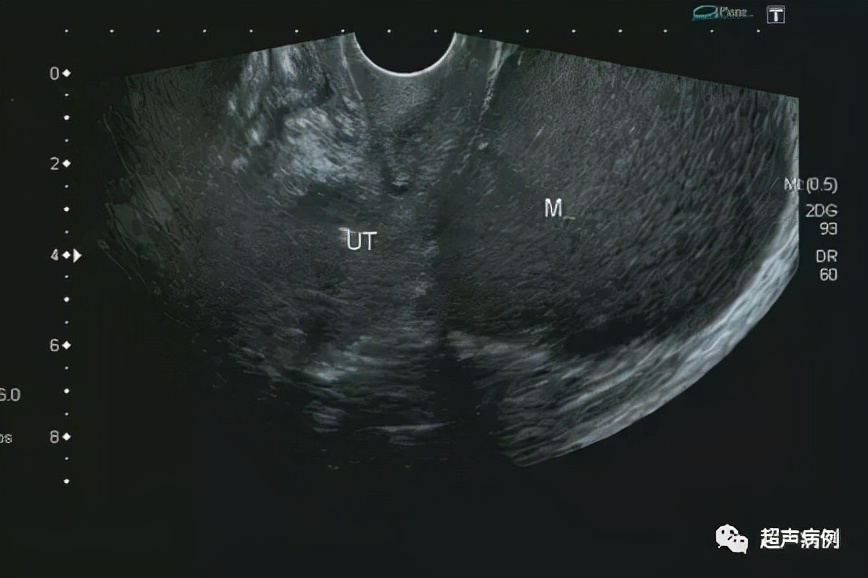

超声检查:

前位子宫,形态、大小正常

在子宫后方盆腔内查见一约10.4x9.7x7.3cm无回声区

形态规则,边界清楚,内透声差,呈毛玻璃样改变

内可见强回声分隔

CDFI:该无回声区内部及周边未见明显血流信号。

双侧卵巢显示不清。